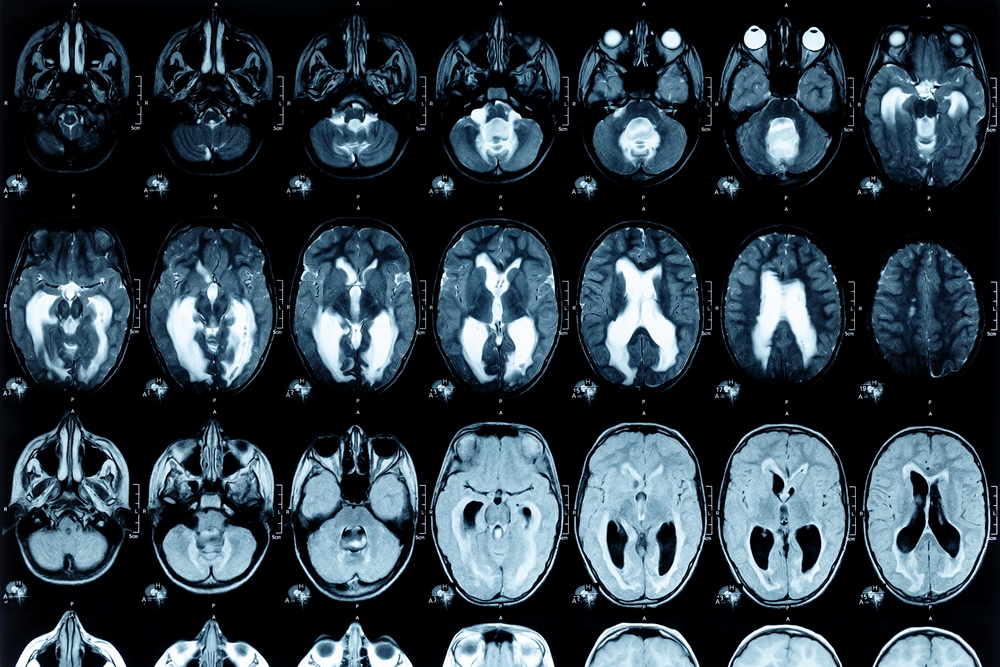

The findings suggest AI could help improve patient selection for clinical trials, potentially reducing the cost of developing new medicines. The model was three times more accurate than standard clinical assessments, which typically rely on memory tests, MRI scans and blood tests.

Developed at the University of Cambridge, the AI system predicts whether and how fast someone at the early stages of cognitive decline will develop Alzheimer’s. It is now being supported by Health Innovation East England to help bring the technology into clinical care.

Researchers applied the model to data from a completed trial of a drug that had failed to show benefits in the overall population. The drug cleared beta amyloid – a protein linked to early Alzheimer’s – in all patients. But only those in the slow-progressing group showed symptom improvements, highlighting the need to target treatment at the right stage.